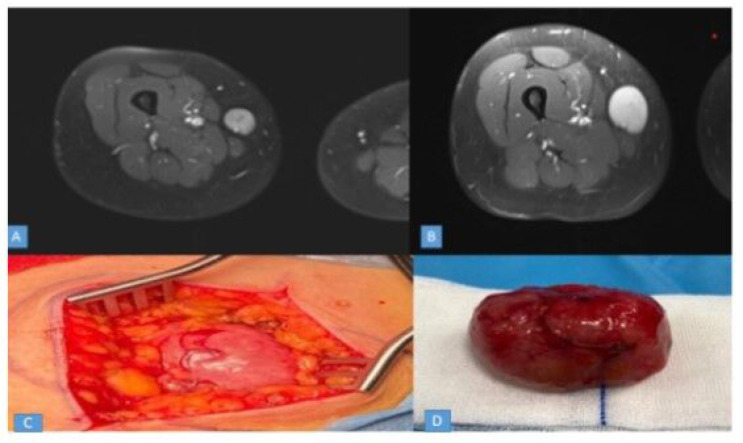

Leiomyomas and schwannomas are both types of rare benign soft tissue tumours. Leiomyomas are more commonly found in the lower limbs than in the upper extremities, while schwannomas are rare peripheral nerve sheath tumours that can occur in different anatomical regions. However, they rarely occur in the saphenous nerve. This case study presents a 41-year-old female patient with a solitary mass lesion located deep in the soft tissue of the anteromedial lower extremity. The physical examination revealed a palpable, elastic-hard, mobile and non-tender mass. Magnetic resonance imaging (MRI) showed an oval-shaped subcutaneous mass on contrast-enhanced T1-weighted sections. The initial MRI images suggested a schwannoma, but the tumour was later confirmed to be a leiomyoma after total enucleation. An immunohistochemical study was performed for differential diagnosis. Solitary mass lesions in the lower extremities can be mistaken for various types of tumours and misdiagnosed and require histopathological examination and good radiological imaging for differential diagnosis. Complete surgical excision is usually a safe and effective treatment for leiomyomas.